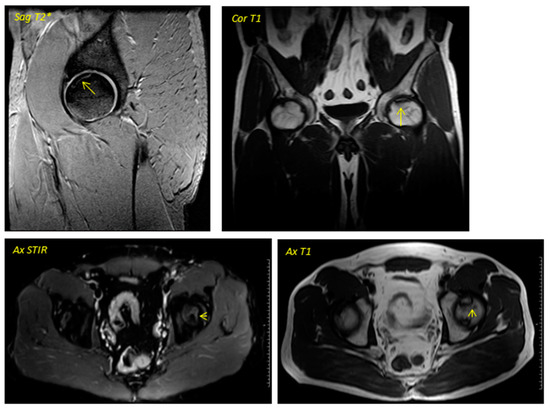

Figure 1. Pre-surgical image corresponding to a 38-year-old male performed in December 2013. The geographic area in the superior anterior region of the left femoral head is delimited by a hypointense line in T1 sequences and hyperintense in T2 sequences in relation to avascular necrosis. No loss of sphericity of the femoral head or joint effusion is evident. It corresponds to type II in the Association Research Circulation Osseous (ARCO) classification.

Regarding the imaging studies, several findings were observed in the radiographic evolution during the 12-month follow-up (Figure 1 and Figure 2). First, changes in the direction appeared in all cases from the sixth month, not being evident in earlier stages. Second, radiographic stabilization was achieved in 62.5% of the patients (n = 5) during the first year after surgery. Third, two patients (25%) showed the progression of the necrotic zone, while in one (12.5%), signs of re-ossification were evident. Despite observing descriptive differences, the p-value was not statistically significant for the latter parameter (p = 0.317).

Regarding the dynamics in the MR images, two patients were baseline in stage IA of the ARCO classification (25%), two in IIA (25%), and four in IIB (50%). In the same way, a stabilization in the staging of the post-surgery images was observed in seven of the eight patients studied (87.5%), with only one case (12.5%) evolving from grade IIB to grade IIIA, presenting subchondral collapse of the femoral head, which was already evident from the sixth month onwards. Descriptively, changes were observed, but they were not statistically significant. No significant variability was observed in the imaging findings between patients.